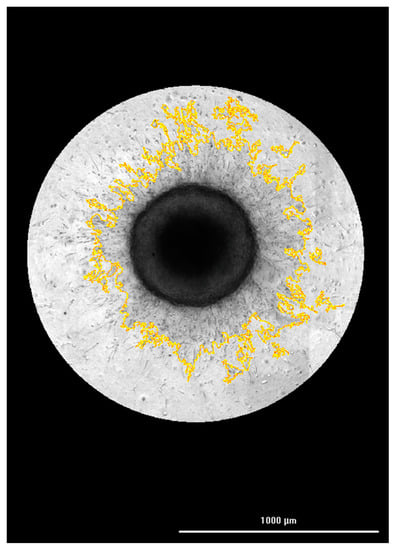

3.2. Correlation of FAM-fTHP-9 Signal with Increased Spheroid Invasion

3.4. Hit Pick Assay Performance Using FAM-fTHP-9 Signal to Trigger Imaging of Test Inhibitor Wells